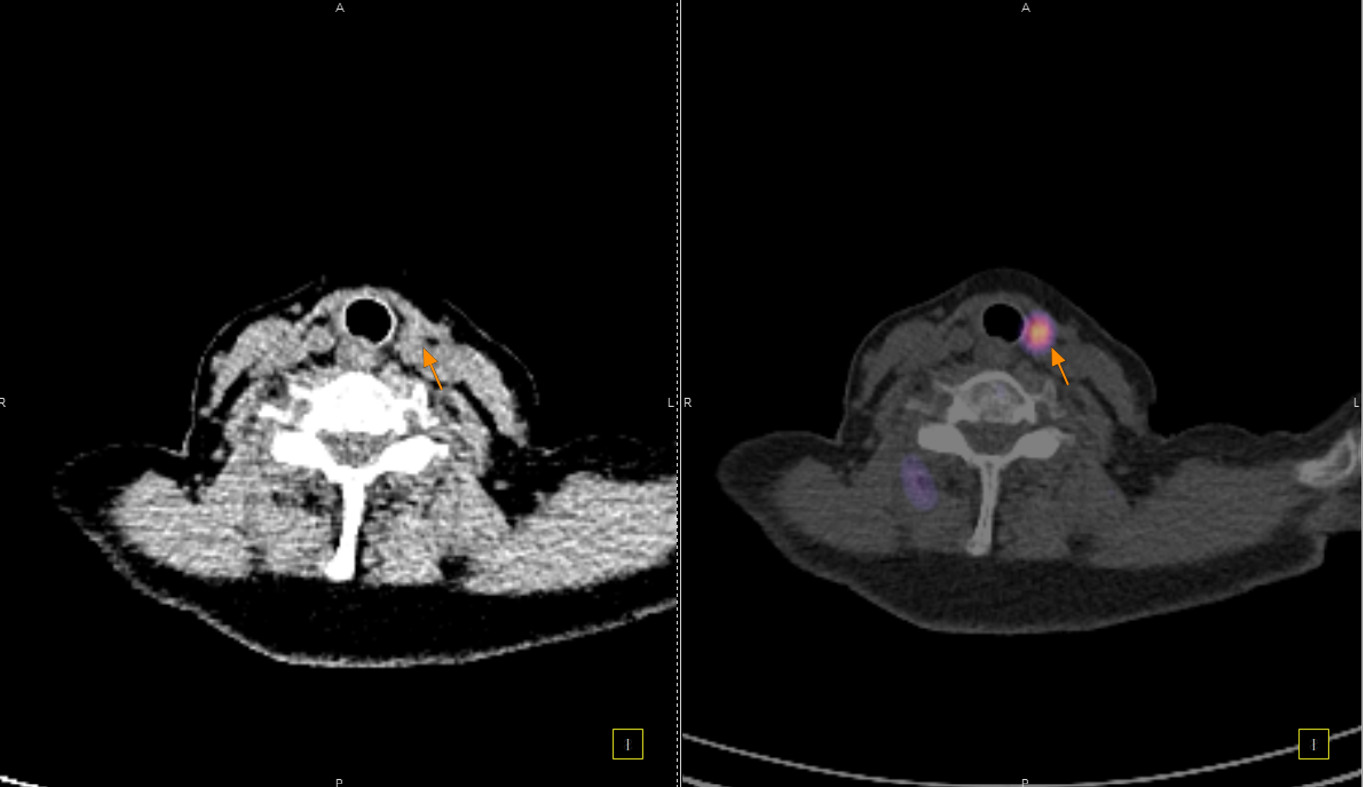

Το Lu-177 PSMA αποτελεί μια στοχευμένη ραδιονουκλιδική θεραπεία για ασθενείς με ορμονοάντοχο μεταστατικό καρκίνο του προστάτη (mCRPC), αξιοποιώντας τη υπερέκφραση του PSMA (Prostate-Specific Membrane Antigen) στα καρκινικά κύτταρα. Προηγείται PSMA PET/CT για ακριβή χαρτογράφηση της νόσου και επιβεβαίωση επαρκούς πρόσληψης του ραδιοφάρμακου. Το Lu-177 PSMA συνδέεται στους PSMA-υποδοχείς, επιτρέποντας στοχευμένη ακτινική δράση υψηλής κυτταροτοξικότητας σε μεταστατικές εστίες οστών και μαλακών μορίων. Η χρήση εξειδικευμένων δοσιμετρικών εργαλείων επιτρέπει την ποσοτική αποτίμηση της δόσης σε κρίσιμα όργανα (π.χ. σιελογόνοι αδένες, νεφροί, μυελός) και στον όγκο, συμβάλλοντας σε εξατομικευμένη θεραπευτική προσέγγιση. Μετά από κάθε κύκλο πραγματοποιείται PSMA PET/CT ή FDG PET/CT (όπου ενδείκνυται), καθώς και στενός αιματολογικός έλεγχος για αξιολόγηση της ανταπόκρισης και των πιθανών τοξικοτήτων. Η θεραπεία έχει αποδειχθεί ιδιαίτερα αποτελεσματική στη μείωση του καρκινικού φορτίου, στη βελτίωση του πόνου, στη μείωση των επιπέδων PSA και στη σημαντική παράταση του προσδόκιμου επιβίωσης σε ασθενείς με εκτεταμένη και ανθεκτική νόσο.